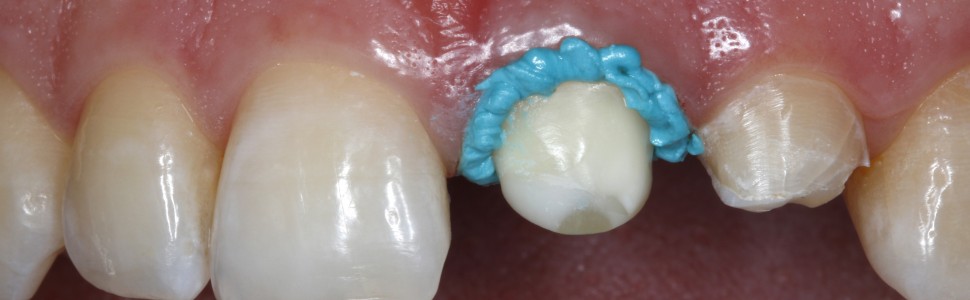

Ryc. 5. Po wprowadzeniu do szczeliny wokół zęba 21 bardzo cienkiej nici retrakcyjnej (w rozmiarze 000) wyciśnięto okrężnym ruchem pastę retrakcyjną przez bardzo cienką, zwężającą się kaniulę (pasta retrakcyjna, VOCO).

Ryc. 6. Pasta retrakcyjna jest łatwa do aplikacji, a zarazem ma dostatecznie gęstą konsystencję, aby pozwalała na dodatkowe poszerzenie szczeliny. Jednocześnie dochodzi do zatrzymania ewentualnego miejscowego krwawienia tkanek miękkich związanego z preparacją.

Ryc. 7. Ząb 21 od strony brzegu siecznego – zwraca uwagę stabilna konsystencja pasty retrakcyjnej, która utrzymuje się na miejscu po aplikacji i nie spływa.